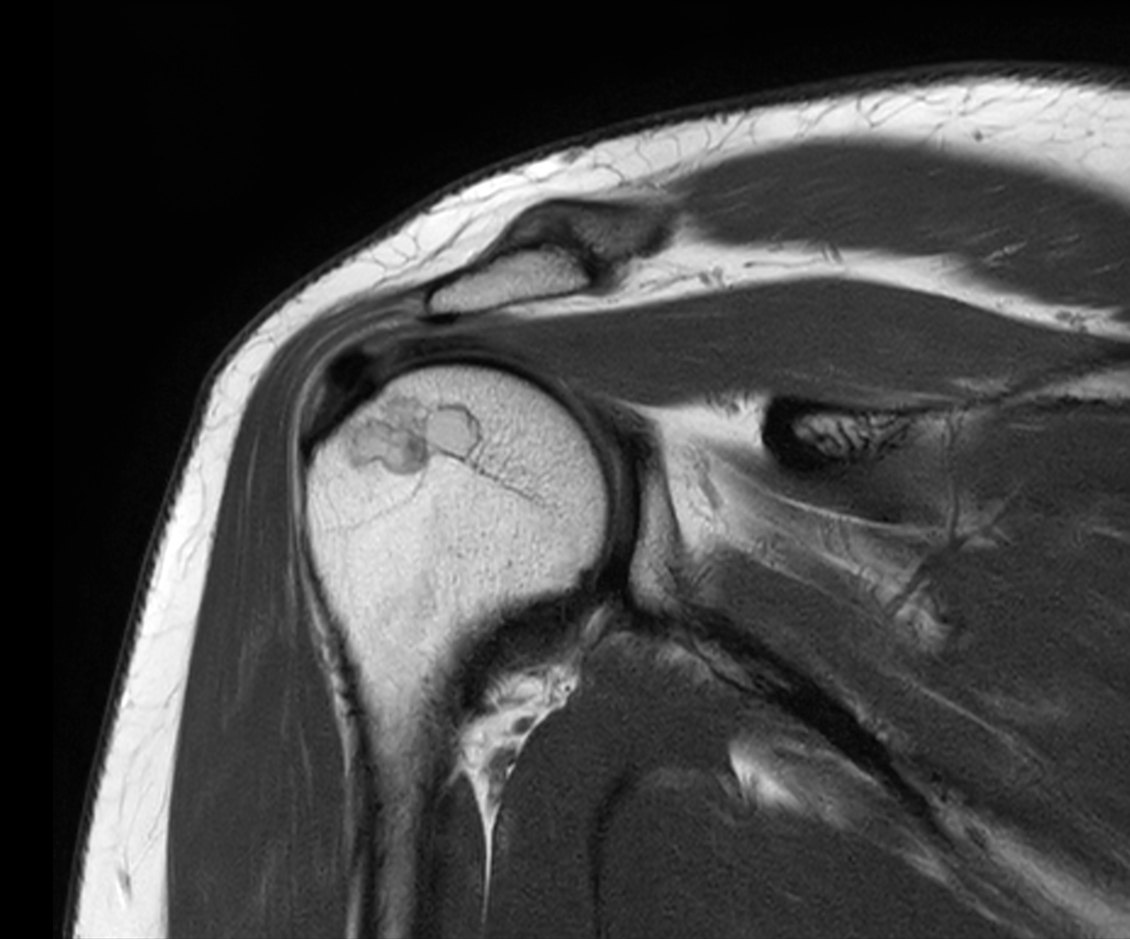

Axial PDw TSE

Axial T1w TSE